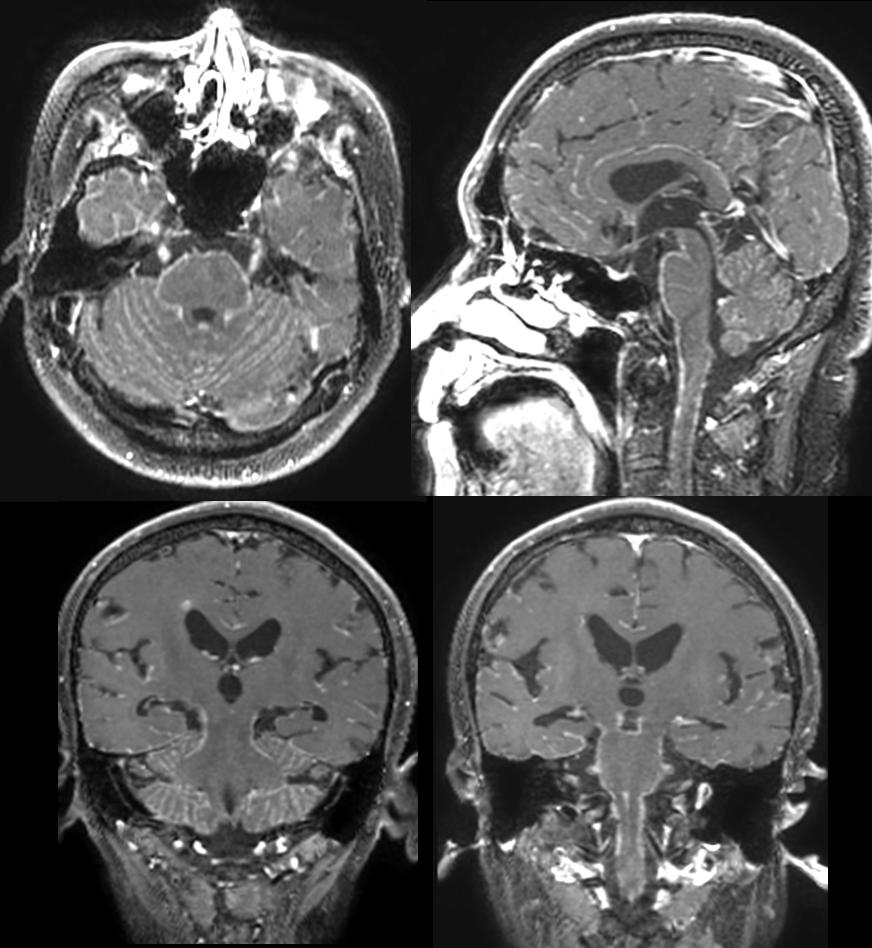

遗憾的是王大叔的病情在治疗7个月后还是进展了。

软脑膜广泛转移:可以看到颅内广泛的软脑膜强化及多发颅神经强化